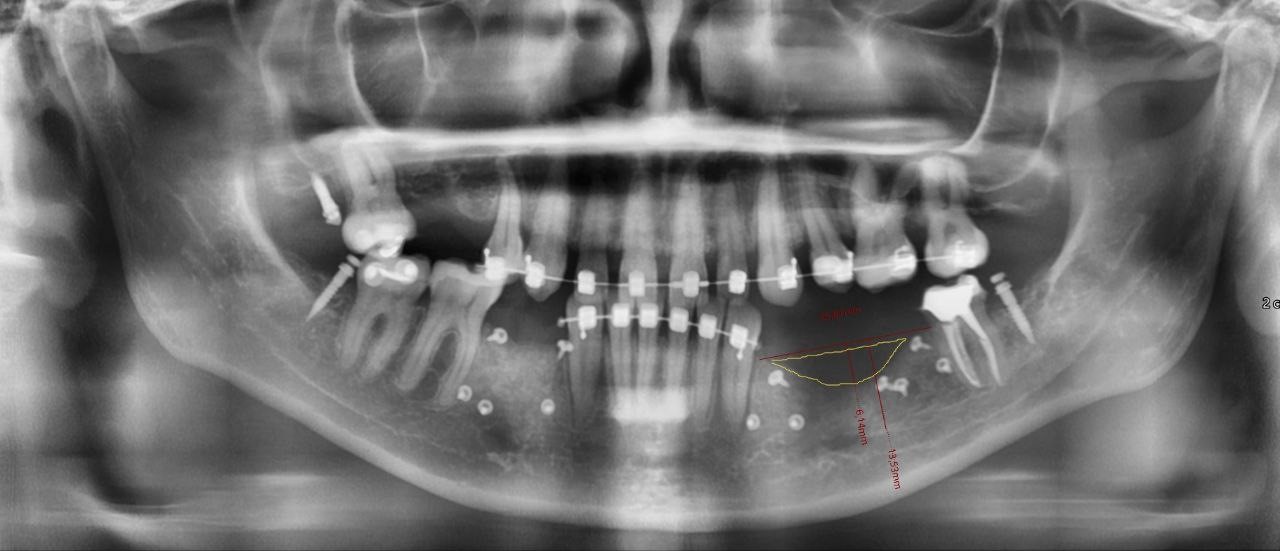

Сегодня у нас ещё один интересный случай симпатичной девушки, у которой не хватало трёх зубов с левой стороны внизу. Кость ушла, виден явный провал. Дважды делала операцию у другого врача, но подсаженная костная ткань не приживалась. Во второй раз вообще развилось воспаление, пришлось всё чистить и делать заново. Осложнялось всё тем, что девушка ещё и носила брекеты, а в этом случае костная пластика, мягко говоря, становится интереснее. Похоже, что именно этого и не учёл предыдущий хирург.

Видны следы от прошлой неудачной операции

Судя по всему, в брекетах как раз и была проблема. Пока они стоят, зубы смещаются. Остеокласты разрушают кость — условно там, куда двигаются зубы. А остеобласты выращивают кость. Когда в область действия этих процессов попадает какая-то инородная кость, она стремительно рассасывается, исчезает. Вот и у неё оба раза вроде всё поставили, а через пару месяцев новой кости нет.

Что же заставило девушку делать остеопластику до окончания ортодонтии? Есть такой нюанс: за два-три месяца до конца ортодонтии импланты уже можно ставить. И даже нужно, чтобы после ортодонтии можно было сразу протезировать, иначе пустоты могут спровоцировать обратное движение зубов. Последние два-три месяца ношения брекетов зубы уже стабилизируются на новом месте, остеокласты перестают разрушать кость, остеобласты регенерируют ткань на своём участке. Так что противопоказаний к имплантации нет. А вот с костной пластикой — проблема.

Мы начали с того, что ортодонт зафиксировал зубы. На это потребовалось около двух месяцев, движение зубов остановилось, мы смогли перейти к остеопластике. Сама операция прошла вполне штатно. И потом мы подождали около полугода, чтобы кость сформировалась и… Вы думаете, мы поставили импланты? Ничего подобного: мы снова поставили брекеты, чтобы она могла доносить их положенные два-три месяца.